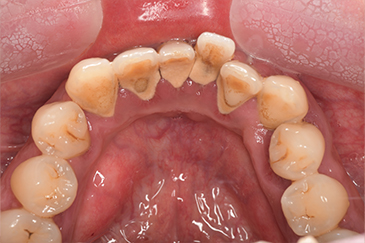

CASE 10

Before①

After①

Before②

After②

基本情報

| 年齢・性別 | 38歳・男性 |

|---|---|

| 主訴 | 下顎 歯石除去したい |

| 治療内容 | スケーリング |

| 治療期間 | 30分 |

| 治療費 | 約1,500円(保険診療) |

| リスク・副作用 | 知覚過敏、歯肉退縮 |

| 治療方針 | 歯肉縁上歯石を除去してから歯肉縁下歯石を除去します。ご自身でのプラークコントロールができるようになったら定期検診に移行します。 |

| 担当者所見 | 半年ぶりの歯科医院の受診。歯石が付きやすいためセルフケアの重要性をお伝えして、定期的にクリーニングを行います。出血率が高く炎症が強いため、今後はセルフケアを強化して歯周病治療を行います。 |